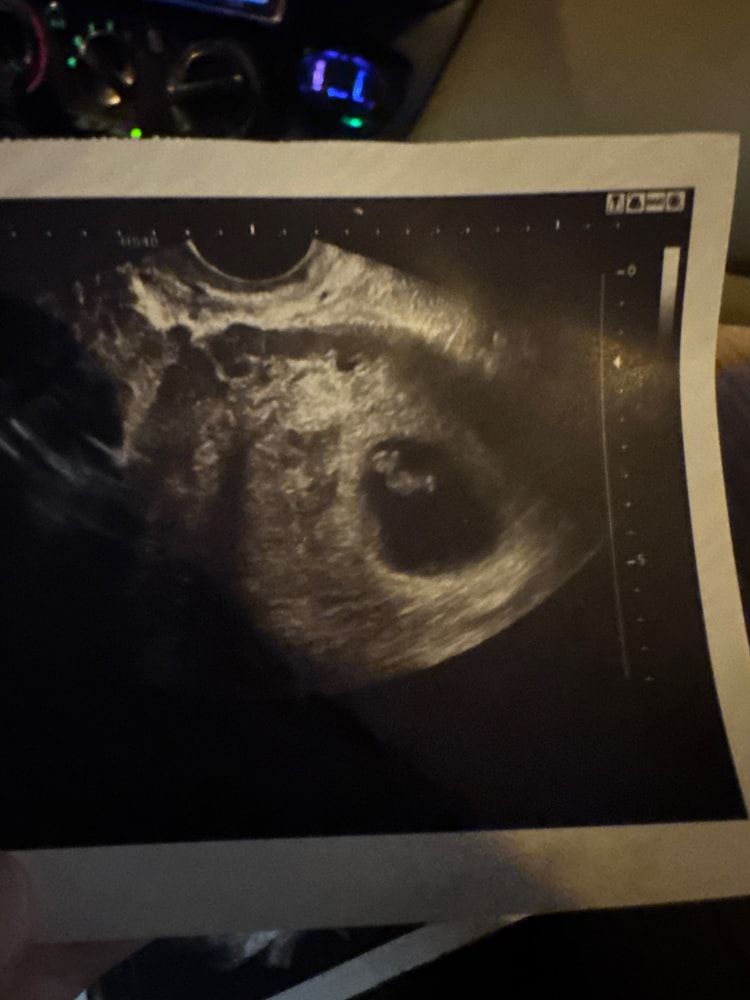

На память узи (ждем пятое пкс в срок🙏)

УЗИ, КТГ, доплерПобывали на узи недавно ,наш(а)малышик(ка)растет )

Рубца на матеке после 4 х КС сейчас 2 , 8 и 11мм ,сказали все прекрасно ) ждем крининг